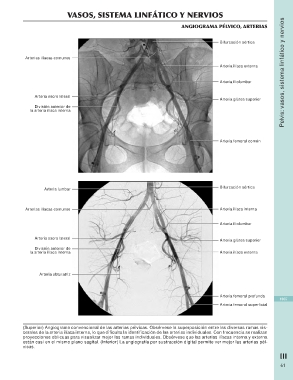

Angiograma pélvico, arterias

Bifurcación aórtica

Arterias ilíacas comunes

Arteria ilíaca externa

Arteria sacra lateral Arteria iliolumbar

División anterior de Arteria glútea superior

la arteria ilíaca interna

Arteria femoral común

Arteria lumbar Bifurcación aórtica

Arteria ilíaca interna

la arteria ilíaca interna Arteria ilíaca externa

Arteria obturatriz

Arteria femoral profunda 1065

Arteria femoral superficial

(Superior) Angiograma convencional de las arterias pélvicas. Obsérvese la superposición entre las diversas ramas vis-

cerales de la arteria ilíaca interna, lo que dificulta la identificación de las arterias individuales. Con frecuencia se realizan

proyeccion es oblicuas para visualizar mejor las ramas individuales. Obsérvese que las arterias ilíacas interna y externa

están casi en el mismo plano sagital. (Inferior) La angiografía por sustracción digital permite ver mejor las arterias pél-

vicas.